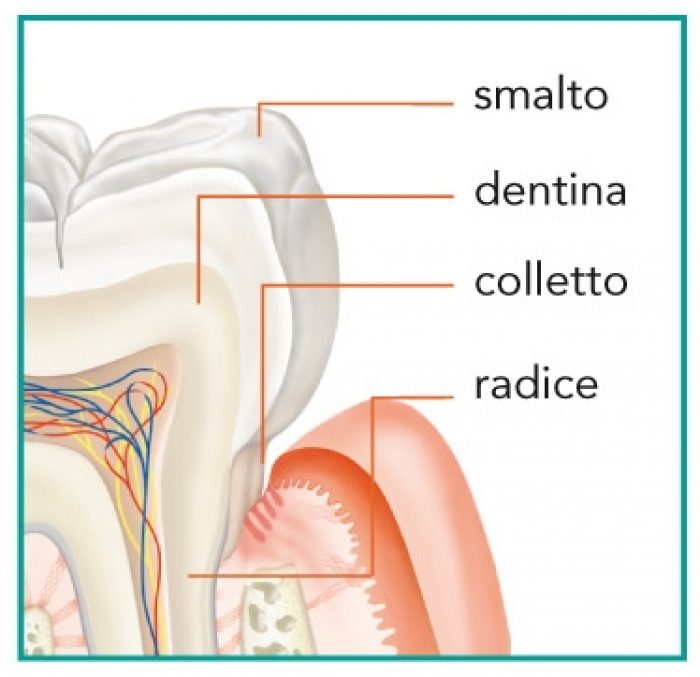

Cosa Sono le Lesioni del Colletto

Le lesioni cervicali sono difetti che si formano nella zona del colletto dentale, l’area di congiunzione tra corona e radice

Perché Si Formano:

- Erosione acida:Bevande acide, reflusso gastroesofageo

- Abrasione meccanica:Spazzolamento aggressivo, dentifrici abrasivi

- Stress occlusale:Bruxismo, malocclusioni dentali

- Flessione dentale:Micro-movimenti sotto carico masticatorio

- Fattori biologici:Recessione gengivale, invecchiamento

- Carie cervicali:Accumulo di placca in zona gengivale